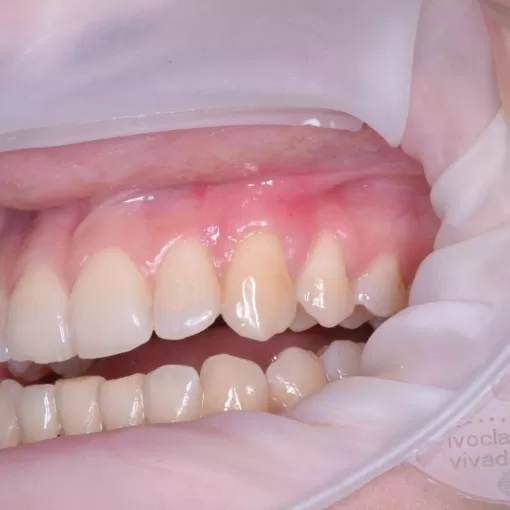

Пациент обратился с целью имплантации в области отсутствующего зуба 4.6. Однако после КЛКТ (3Д) исследования был обнаружен воспалительный процесс (киста) в области соседнего зуба 4.7 (рис. 1).